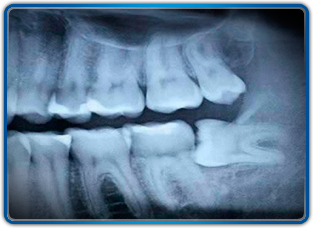

A wisdom tooth, in humans, is any of the usually four third molars. Wisdom teeth usually appear between the ages of 17 and 25.

Wisdom teeth commonly affect other teeth as they develop, becoming impacted or "coming in sideways". They are often extracted when this occurs.

Wisdom teeth are extracted for two general reasons: either the wisdom teeth have already become impacted, or the wisdom teeth could potentially become problematic if not extracted. Potential problems caused by the presence of properly grown-in wisdom teeth include infections caused by food particles easily trapped in the jaw area behind the wisdom teeth where regular brushing and flossing is difficult and ineffective. Such infections may be frequent, and cause considerable pain and medical danger.

Other reasons wisdom teeth are removed include misalignment which rubs up against the tongue or cheek causing pain, potential crowding or malocclusion of the remaining teeth (a result of there being not enough room on the jaw or in the mouth), as well as orthodontics.